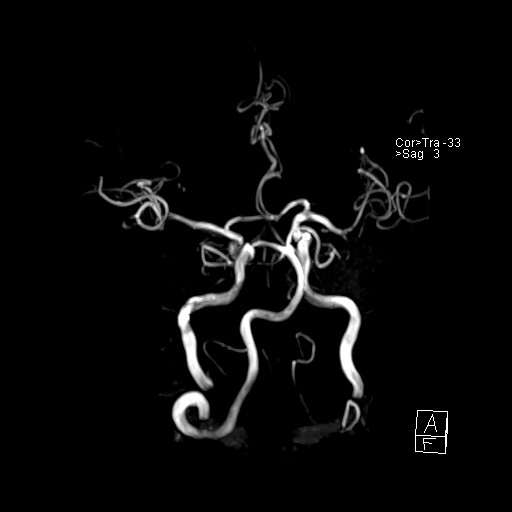

239716 - VILLANUEVA, WILLIAM A. - Number 1 |

|

239716 - VILLANUEVA, WILLIAM A. - Number 1 |